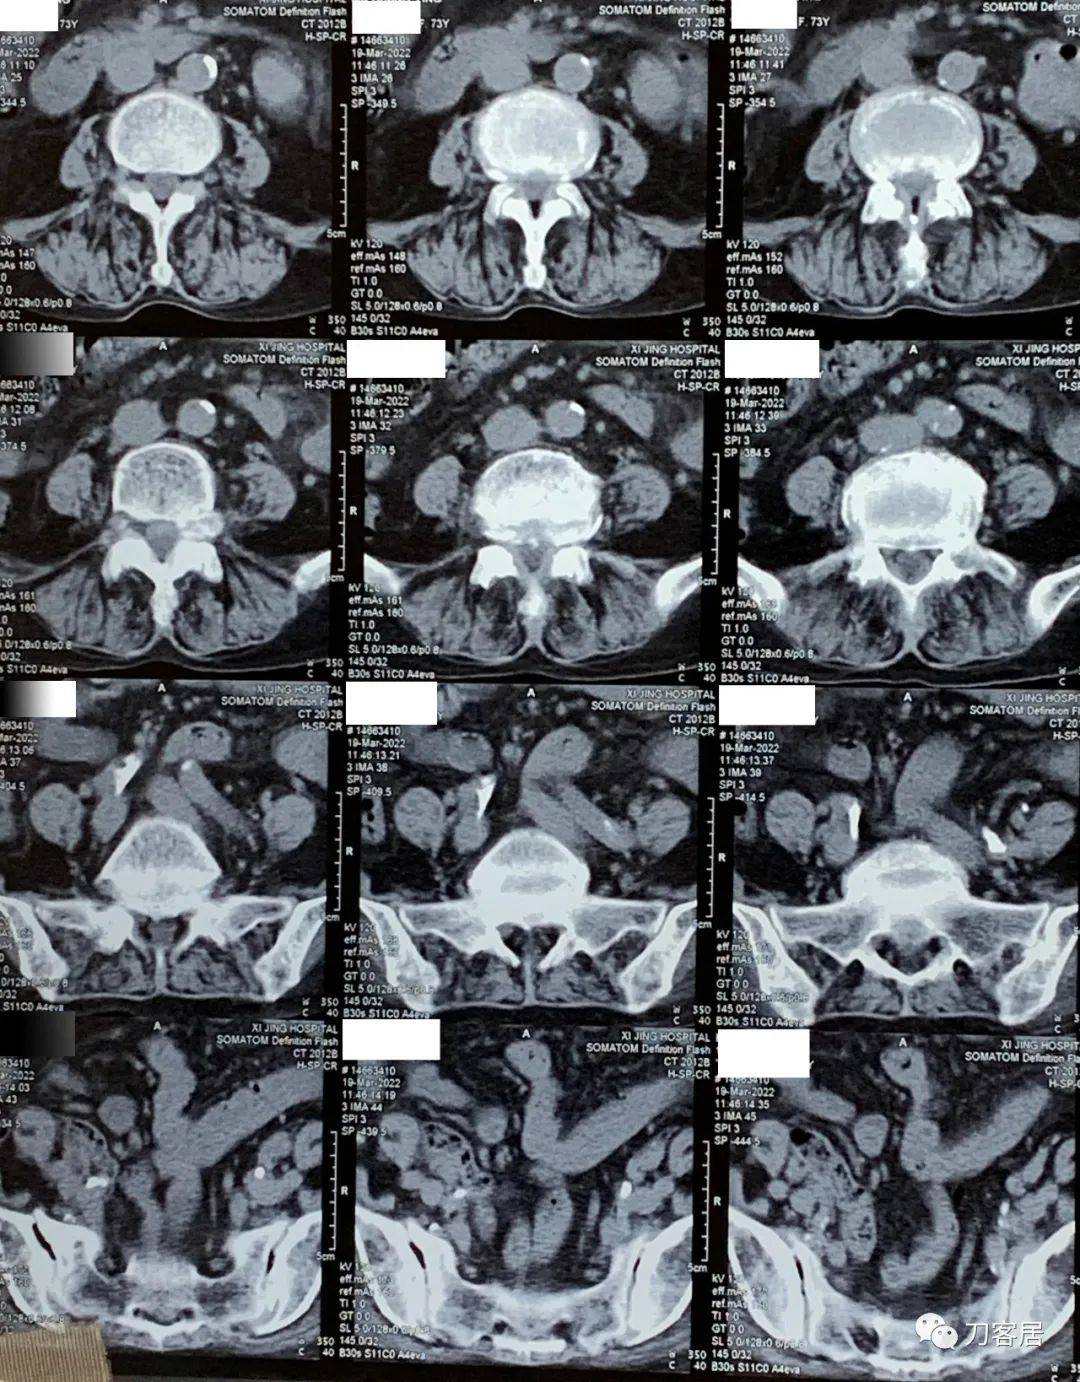

3月19日在我院神经外科门诊就诊时,做了腰椎CT平扫。腰椎CT提示腰4-5,腰5骶1椎间盘突出,腰4-骶1椎管狭窄。

图1. 20220319西京医院腰椎CT01

图2. 20220319西京医院腰椎CT02

图3. 20220319西京医院腰椎CT03

图4. 20220319西京医院腰椎CT04